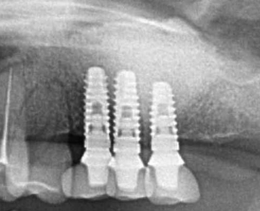

サイナスリフト症例(治療前後のCTもしくはパノラマ写真)

↓

↓